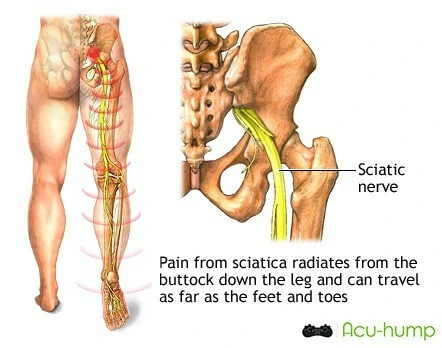

The pain experienced with piriformis syndrome can be quite severe and may feel like a sharp, stabbing sensation. The pain is often located in the buttock area, particularly towards the back and side of the hip, and may spread down the back of the thigh and into the calf, ankle or foot. Numbness or tingling in the leg may also be present, along with a feeling of weakness or fatigue in the leg.

These 2 conditions share similar symptoms, however, sciatica is characterized by a compression of the sciatic nerve, which runs from the lower back, through the buttocks, and down into the leg.

It is usually a secondary condition, caused by a herniated disk, spinal stenosis, or other spinal conditions, or as a result of piriformis syndrome.

Sciatica is generally classified as either originating in the buttocks or lower back, called piriformis syndrome or sciatica respectively. Piriformis syndrome is caused by the compression of the sciatic nerve by the buttock muscles, while other causes of sciatica involve compression of the nerve in the lower back.

Unlike sciatica originating from the spine, piriformis syndrome usually starts in the buttocks and, in severe cases, may radiate down to the lower back.

Sciatica commonly affects both sides of the body with varying degrees of intensity. The symptoms of piriformis syndrome are usually limited to one side of the buttock area.

It is important to differentiate between piriformis syndrome and sciatica1, as the treatment options vary depending on the cause of pain. A healthcare provider can perform physical examinations, imaging tests, and nerve conduction studies to diagnose the underlying condition and develop a treatment plan.